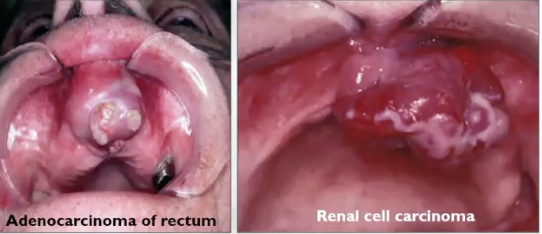

What is metastatic disease?

It is more common of a carcinoma than a sarcoma

What is the difference between carcinoma and sarcoma?

Sarcoma = origin is mesenchymal stem cells (bone, cartilage, adipose tissue, fat, skeletal muscle, smooth muscle)

Carcinoma = origin of the epithelium (most common is squamous cell carcinoma)

If metastatic disease does occur, where will it be?

2/3 are in bone (80% mandible > maxilla)

1/3 in soft tissue (most commonly gingiva)

Common origin of gnathic metastasis:

Breast

Lung

Thyroid

Prostate

Kidney

What is this

Metastatic nasopharyngeal carcinoma

Metastatic small cell carcinoma of the lung